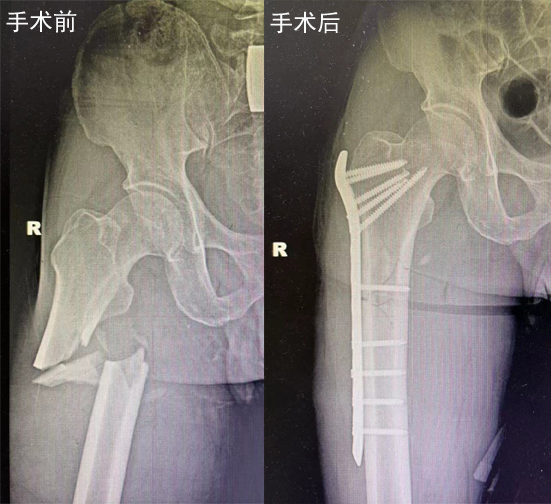

黄延峰手术治疗案例